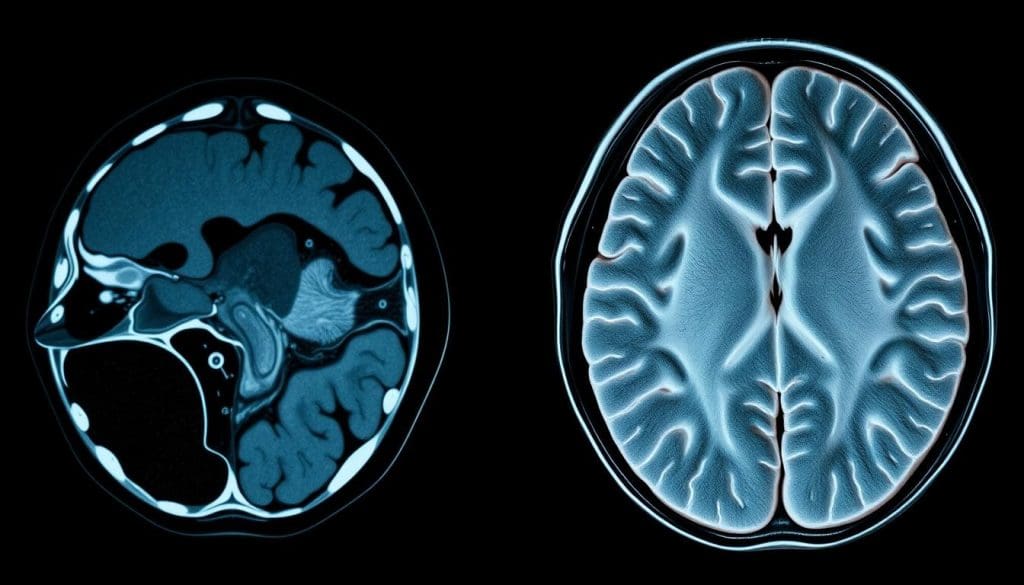

Comparing Image Quality and Diagnostic Capabilities

CT Scan Image Characteristics

CT scans are great for showing bones clearly. They’re often used in emergencies to spot bone breaks or bleeding quickly. CT scans use X-rays to make detailed images of the body, which can be turned into 3D if needed.

They’re very good at finding calcium and bone issues. But, they’re not as good as MRI for soft tissues.

MRI Image Characteristics

MRI is better for soft tissues like tumors, infections, and inflammation. It gives detailed brain images without harmful radiation. This makes MRI very useful for brain studies.

Doctors say MRI is key for brain imaging because it shows soft tissue changes well.

Tissue Contrast and Resolution Differences

CT scans and MRI show different things. CT scans are better for bones and bleeding. MRI is better for soft tissues. The right choice between CT and MRI depends on the diagnostic question and the tissue type.